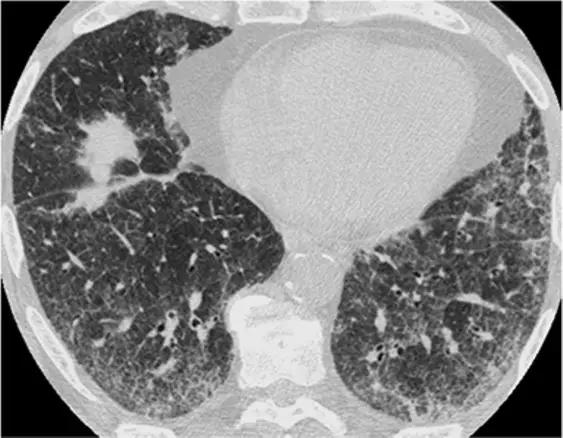

3、磨玻璃影模式

HRCT上的磨玻璃样改变被定义为不透明的薄雾影增加,并保留了支气管和血管标记。经典疾病:亚急性过敏性肺炎(HP),其特征是磨玻璃样混浊的对称斑片或弥散性双侧区域,伴有边界义不清的小叶中心型结节。有助于将亚急性HP与其他相似疾病分开的特征是,在吸气图像和气管呼气图像上,小叶区域的衰减和多血管影。磨玻璃样的最常见的鉴别疾病是呼吸性毛细支气管炎相关的间质性肺病(RB-ILD)、脱屑性间质性肺炎(DIP)和肺囊虫性肺炎。

RB-ILD可表现为中度到广泛性的双侧磨玻璃影,边界不清的小叶中心型结节,支气管壁增厚。有时,在肺基部可能会出现轻微的网状结构。区分RBILD和亚急性HP的线索是RB-ILD存在上叶轻度肺气肿,HP吸烟者存在吸烟习惯的改变。

*RB-ILD 上叶水平的HRCT显示弥散的“毛玻璃样”,小叶透亮区代表伴随的小叶肺气肿。